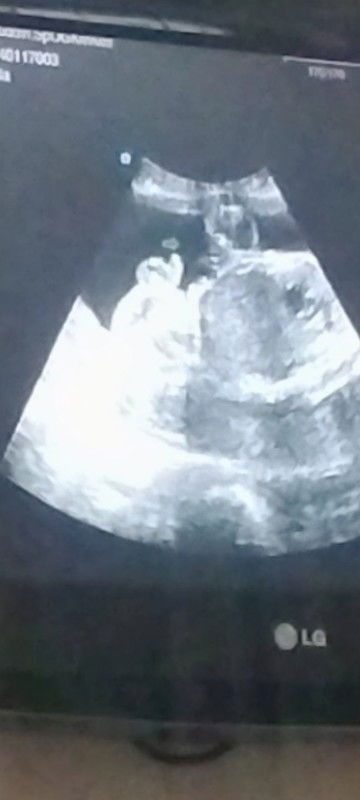

JK laki-laki saat usg 26 week

maaf tanya bun. kata dokter foto ini jelas menunjukkan kalau JK baby laki-laki soalnya baru pertama kali di lihat USG JK. apakah itu sudah sangat jelas ya bun??#seriusnanya #bantusharing #ingintahu #UsgJK

itu loh keliatan bgt monasnyaa